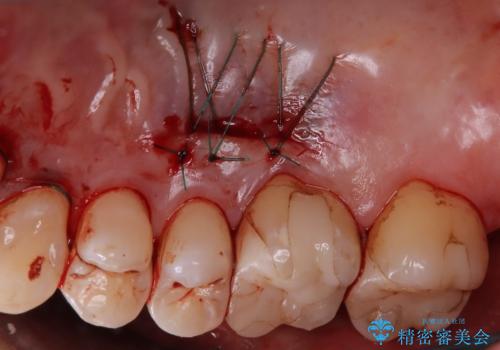

- 歯肉退縮にお悩みの患者様に対して、根面被覆術(結合組織移植術)を行いました。

歯肉移植(結合組織移植術)とは、患者様ご自身の歯肉を移植することで、後退した歯肉を補う治療法です。具体的には、上あごの内側から採取した健康な歯肉を、歯肉退縮が見られる部分に移植します。この手術により、後退した歯肉が再び歯の根元を覆うようになり、見た目も改善されます。

- 外科手術のため、術後に痛みや腫れ、違和感を伴います